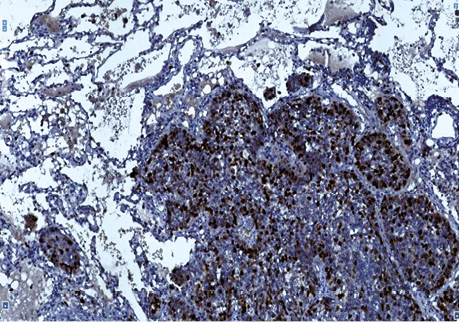

Так, у гістологічних препаратах залозистої карциноми (рис. 1, 2) різного ступеня диференціювання у 2 (13,3%) хворих установлений аденосквамозний тип РЛ. За макроскопічними даними у 2 (13,3%) хворих пухлинні вузли «зливалися» між собою, тобто не мали чітких периферичних контурів, ще у двох (13,3%) — визначався беззаперечний дифузний ріст залозистого РЛ. Крім того, в усіх гістологічних препаратах 15 хворих визначені ділянки бронхіолоальвеолярного типу РЛ. Імуногістохімічні дослідження з моноклональними антитілами (Кі-67 і PCNA) дозволили підтвердити початок росту НДКРЛ від базальної мембрани (рис. 3, 4).

Рис. 3. Залозистий рак. Позитивна імуногістохімічна реакція з PCNA в базальних клітинах пухлини, яка росте в альвеолах. Гістологічний препарат, ×400

Рис. 4. Плоскоклітинний рак. Позитивна імуногістохімічна реакція з Кі-67 в базальних клітинах пухлини, яка росте в альвеолах. Гістологічний препарат, ×400